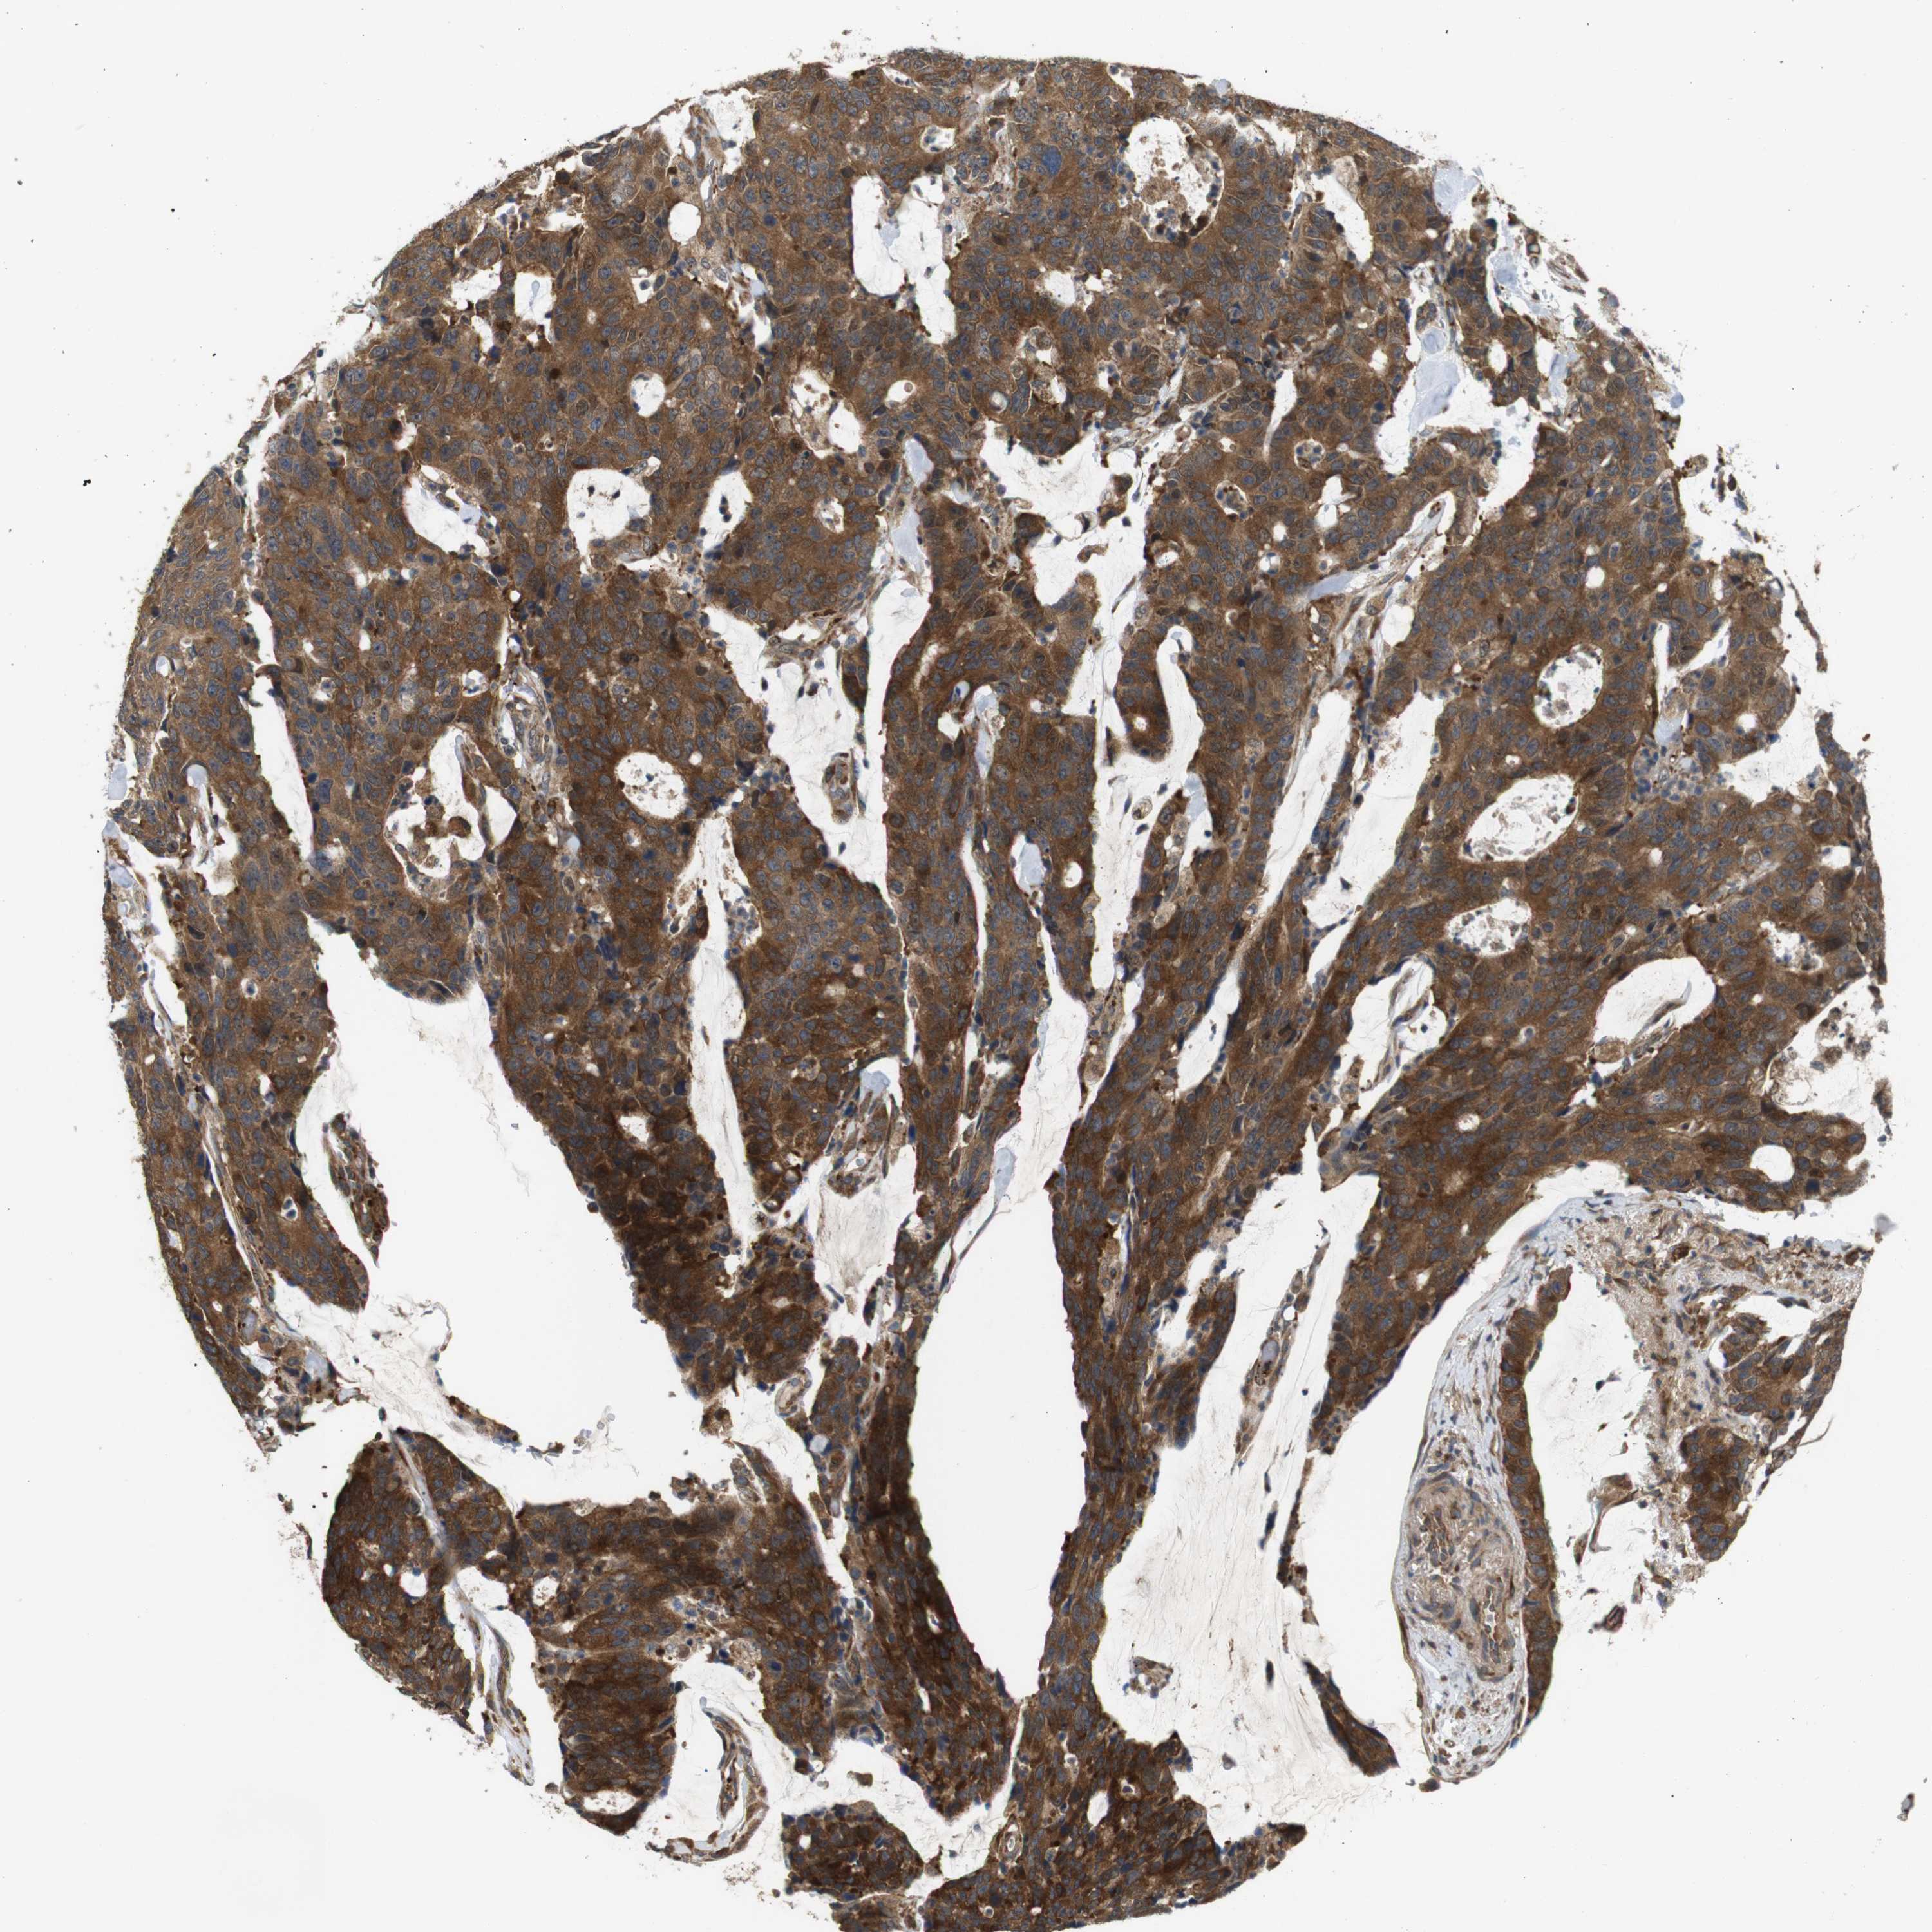

CANCER COLORECTAL CANCER Show tissue menu

Colorectal cancer

Human cancer

Colon adenocarcinoma